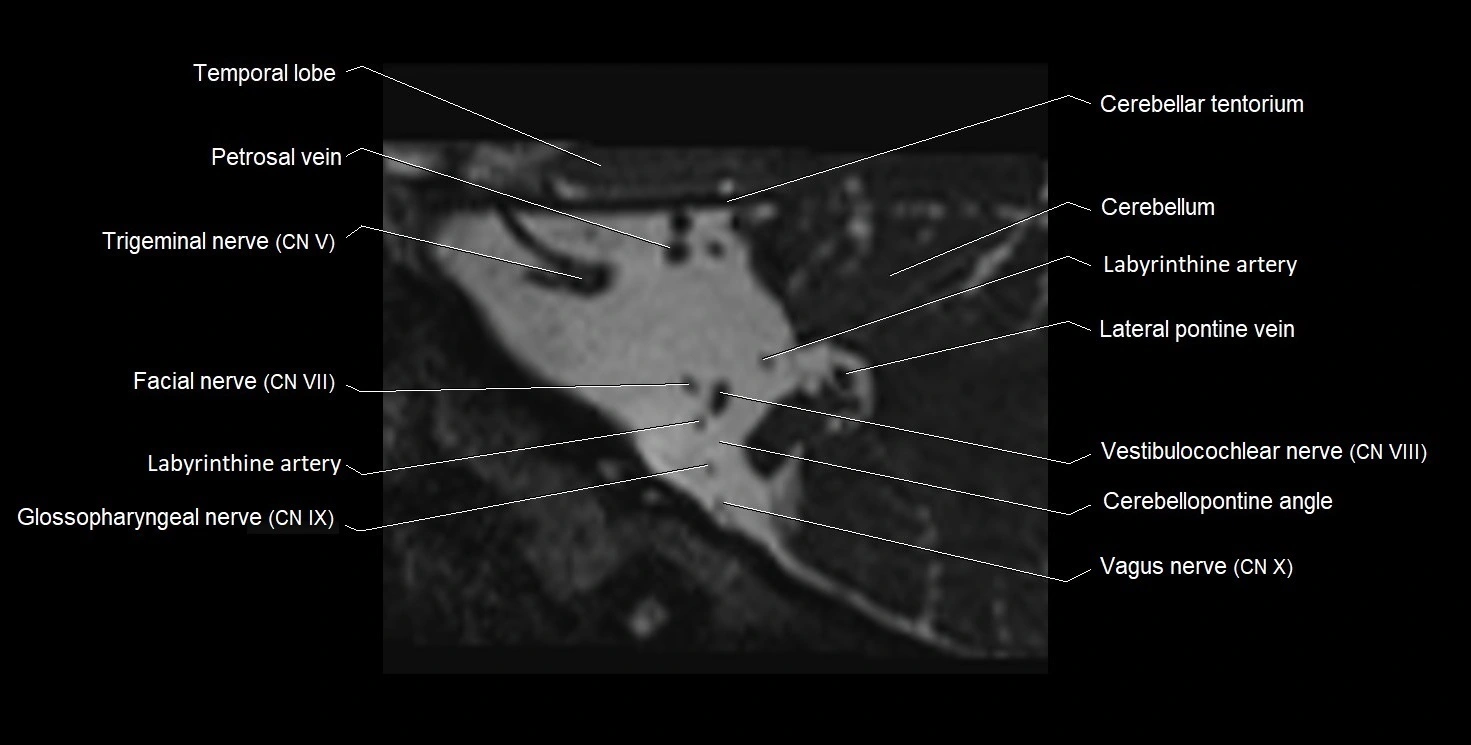

MRI Appearance

• The abducens nerve is a small, thin, linear structure

• Best visualized on high-resolution T2-weighted 3D MRI sequences (e.g., FIESTA or CISS)

• Seen as a hypointense (dark) line running from the brainstem at the pontomedullary junction, traversing the prepontine cistern, and entering Dorello’s canal under the petrosphenoidal ligament, then into the cavernous sinus, and finally the orbit

• May be challenging to visualize in standard MRI due to its small size

• Pathology may be inferred by absence, displacement, or enhancement of the nerve

MRI images

image